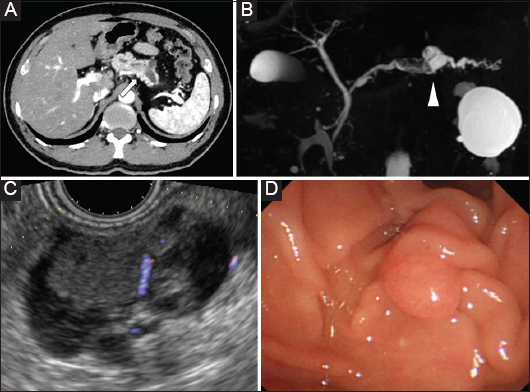

View Of Recurrent Intraductal Papillary Mucinous Neoplasms Of The Pancreas Mimicking Ampullary Cancer Annals Of Gastroenterology